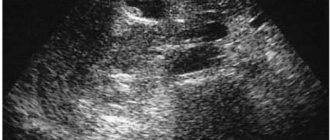

УЗИ при обследовании почки дает сигнал в виде белого пятна на органе о том, что внутри его присутствует какое-либо инородное тело или новообразование.

Гиперэхогенные почки на ультрасонограмме

Гиперэхогенные включения на УЗИ